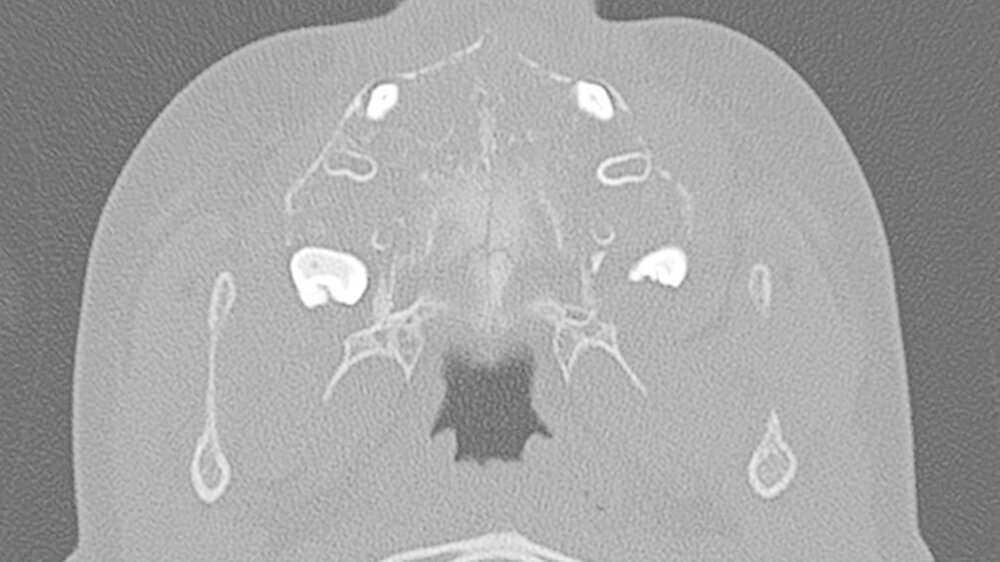

Da die konventionelle Röntgenuntersuchung keinen wegweisenden Befund zeigte, wurde die bildgebende Diagnostik um eine Dünnschicht-Computertomografie (HR-CT) des Mittelgesichts, eine Magnetresonanztomografie (MRT) des Kopf-Hals-Bereichs und eine Halssonografie erweitert.

In der HR-CT zeigten sich Arrosionen am Oberkiefer und Kieferhöhlenboden sowie eine irreguläre Knochenbinnenstruktur mit Rarefizierung der Kochentrabekel und Demineralisation im Mittelgesichtsbereich, weiterhin eine Verschattung der Kieferhöhlen beidseits (Abbildungen 2 und 3).